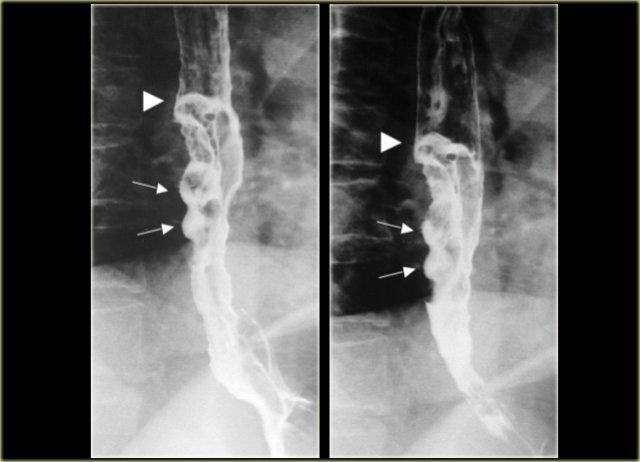

Các hình ảnh này của một bệnh nhân có ung thư dạng giãn tĩnh mạch.

Hình ảnh các khuyết thuốc không thay đổi gợi ý đây là khối u hơn là giãn tĩnh mạch thực sự.

Lưu ý bờ trên sắc nét của tổn thương và ổ loét (mũi tên)

Ngoài cùng bên trái là hình ảnh của một bệnh nhân có ung thư dạng giãn tĩnh mạch.

Các thùy dài mô phỏng hình ảnh giãn tĩnh mạch nhưng không thay đổi trong quá trình soi huỳnh quang.

Lưu ý các nếp niêm mạc không đều, lớn và khối mô mềm (mũi tên) ở đáy vị

Kế bên là hình ảnh của một bệnh nhân có ung thư lan tràn bề mặt.

Tổn thương lan tràn bề mặt rộng liên quan đến đoạn thực quản xa.

Hình ảnh này có thể gặp ở cả tổn thương sớm lẫn tổn thương tiến triển.